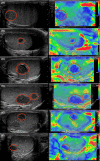

The purpose of this study was to evaluate prospectively the accuracy of qualitative and strain ratio elastography (SE) in the differential diagnosis of non-palpable testicular lesions. The local review board approved the protocol and all patients gave their consent. One hundred and six patients with non-palpable testicular lesions were consecutively enrolled. Baseline ultrasonography (US) and SE were correlated with clinical and histological features and ROC curves developed for diagnostic accuracy. The non-palpable lesions were all ≤1.5 cm; 37/106 (34.9%) were malignant, 38 (35.9%) were benign, and 31 (29.2%) were non-neoplastic. Independent risk factors for malignancy were as follows: size (OR 17.788; p = 0.002), microlithiasis (OR 17.673, p < 0.001), intralesional vascularization (OR 9.207, p = 0.006), and hypoechogenicity (OR, 11.509, p = 0.036). Baseline US had 89.2% sensitivity (95% CI 74.6-97.0) and 85.5% specificity (95% CI 75.0-92.8) in identifying malignancies, and 94.6% sensitivity (95% CI 86.9-98.5) and 87.1% specificity (95% CI 70.2-96.4) in discriminating neoplasms from non-neoplastic lesions. An elasticity score (ES) of 3 out of 3 (ES3, maximum hardness) was recorded in 30/37 (81.1%) malignant lesions (p < 0.001). An intermediate score of 2 (ES2) was recorded in 19/38 (36.8%) benign neoplastic lesions and in 22/31 (71%) non-neoplastic lesions (p = 0.005 and p = 0.001 vs. malignancies). None of the non-neoplastic lesions scored ES3. Logistic regression analysis revealed a significant association between ES3 and malignancy (χ2 = 42.212, p < 0.001). ES1 and ES2 were predictors of benignity (p < 0.01). Overall, SE was 81.8% sensitive (95% CI 64.8-92.0) and 79.1% specific (95% CI 68.3-88.4) in identifying malignancies, and 58.6% sensitive (95% CI 46.7-69.9) and 100% specific (95% CI 88.8-100) in discriminating non-neoplastic lesions. Strain ratio measurement did not improve the accuracy of qualitative elastography. Strain ratio measurement offers no improvement over elastographic qualitative assessment of testicular lesions; testicular SE may support conventional US in identifying non-neoplastic lesions when findings are controversial, but its added value in clinical practice remains to be proven.